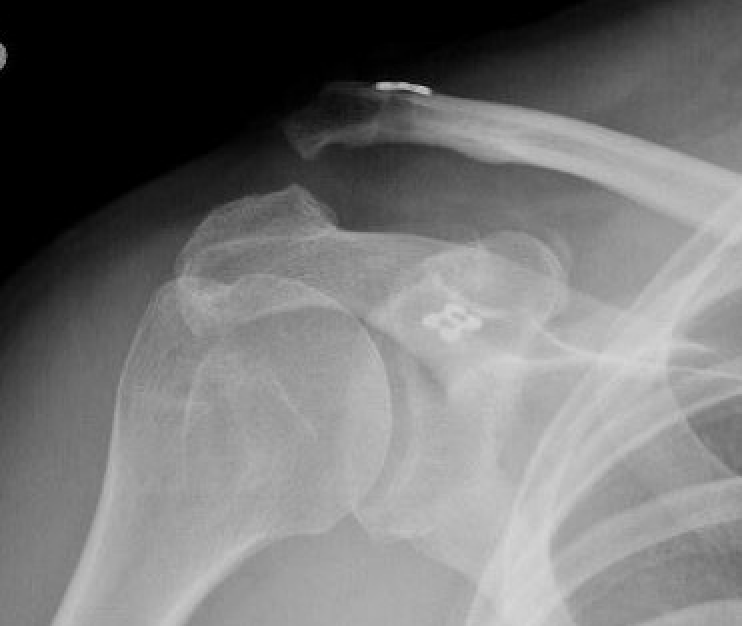

Hook plate

Technique

Reduction of ACJ

- hook under posterior acromion

- allows CC ligaments to heal

- need to remove plate at 4 - 6 months